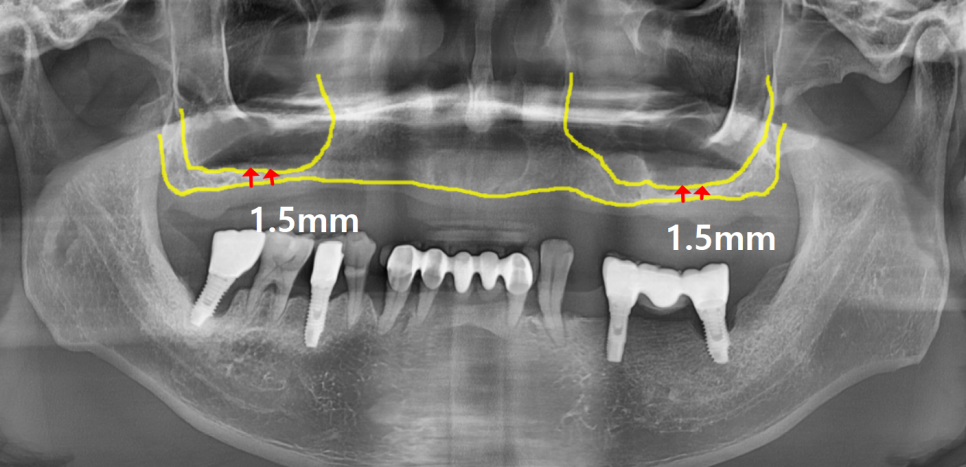

임플란트를 안정적으로 심으려면

뼈의 높이가 최소 7~8mm는 되어야 합니다.

그런데 이 환자분은 1.5mm밖에 남지 않은 상태였습니다.

그럼 나머지 깊이는 어떻게 채울까요?

바로 상악동 거상술을 통해 해결합니다.

상악동 거상술은

상악동의 얇은 막(계란 속 껍질처럼 얇은 조직)을

조심스럽게 들어 올리고,

그 아래 공간에 인공뼈를 채워

새로운 뼈 높이를 만들어주는 수술입니다.